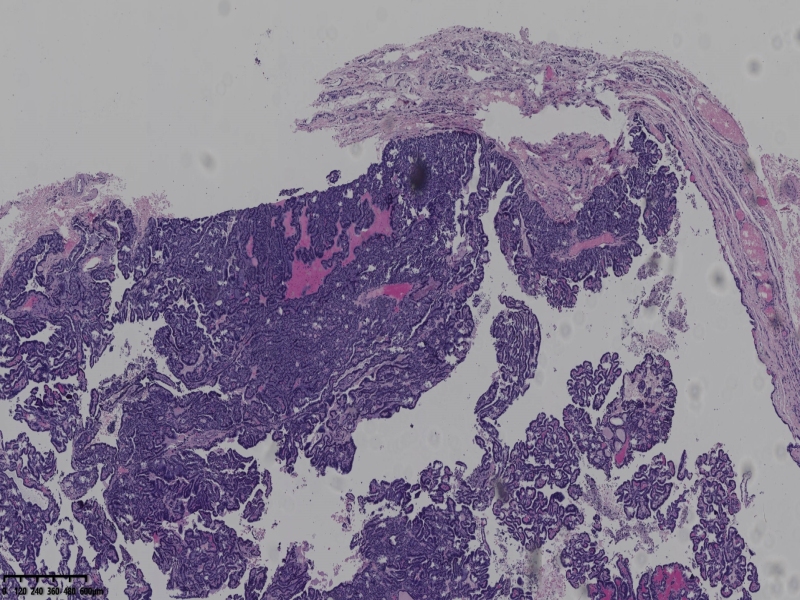

男、69、甲状腺左叶肿物,部分为囊性,囊内可见乳头状结构,上皮核重叠,没有核沟,没有毛玻璃样改变,没有核内假包涵体。255427

部分区域瘤组织与周围甲状腺组织分界明显,没有包膜样结构,滤泡结构为主,细胞异型明显。

会诊结果:(左叶甲状腺近峡部)甲状腺肿瘤,考虑为具有RAS核的乳头状癌,建议免疫组化及基因检测。